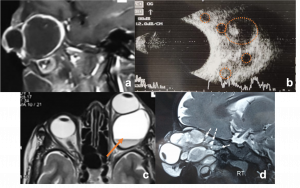

Retinoblastoma. a) Contrast-enhanced T1WI axial MRI image showing an enhancing right intraocular mass with no extraocular extension (orange arrow) b) T2WI axial MRI image showing hypointense signal (blue arrow) c) USG (B/A) showing intraocular mass lesion with specks of calcification corresponding to the spikes of A-scan. | |

| Uveal Melanoma[45] | Middle aged adults | Dimunition of vision, assoicated with exudative retinal detachment. | MRI is the investigation of choice.

T1 hyperintensity T2- hypointense It enhances brightly on contrast |